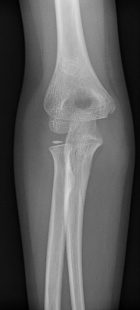

7 year old male fell a week ago, noticed a mass on his elbow

Zoom image: Radiological image Radiological image.